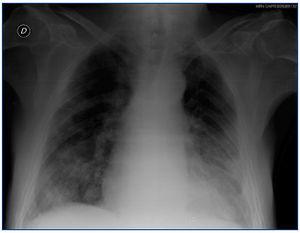

5. Radiografía de tórax: patrón alvéolo-intersticial bilateral con disposición periférica y de distribución algodonosa que no mejora tras ultrafiltración (figura 1).

Figura 1. Radiografía de tórax realizada al ingreso.